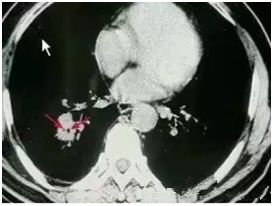

●高危結(jié)節(jié)

●結(jié)節(jié)呈毛栗子樣,周圍有角(棘突)和細(xì)小毛刺生長(zhǎng)

●結(jié)節(jié)如月亮,周圍有一圈暈

●結(jié)節(jié)呈分葉狀

●多位于上葉結(jié)節(jié)

●結(jié)節(jié)里有較粗的血管牽扯進(jìn)來(lái)

●結(jié)節(jié)里有透亮的小空泡(空氣支氣管征)

●結(jié)節(jié)外圍有胸膜牽拉征象(臍凹征)

●隨訪3—6月以上,結(jié)節(jié)明顯增大或內(nèi)部密度增高

對(duì)于以上的高危結(jié)節(jié)應(yīng)由胸外科、腫瘤內(nèi)科、呼吸科和影像醫(yī)學(xué)科醫(yī)生集體會(huì)診,決定是否需要進(jìn)一步檢查(包括支氣管鏡、CT增強(qiáng)掃描、經(jīng)皮穿刺活檢等)明確診斷,以及采取什么方法治療。

對(duì)高度懷疑為惡性者且適合于外科手術(shù)者,首選手術(shù)治療。對(duì)肺癌可能性小的病例可抗炎治療7—10天,休息一周后復(fù)查,結(jié)節(jié)增大或無(wú)變化,可進(jìn)入臨床治療,結(jié)節(jié)縮小可動(dòng)態(tài)隨訪。